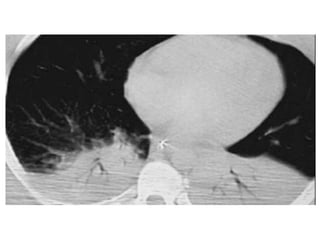

• Pneumothorax

• Sonogram (ultrasound) – Sonogram to look for

pneumothorax, mainstem intubation, etc.